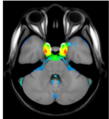

A statistical atlas of cerebral arteries

Magnetic resonance angiography (MRA) can capture the variation of cerebral arteries with high spatial resolution. These measurements include valuable information about the morphology, geometry, and density of brain arteries, which may be useful to identify risk factors for cerebrovascular and neurological diseases at an early time point. However, this requires knowledge about the distribution and morphology of vessels in healthy subjects. the statistical arterial brain atlas described in this work is a free and public neuroimaging resource that can be used to identify vascular morphological changes. The atlas was generated based on 544 freely available multi-center MRA and T1-weighted MRI datasets. the arteries were automatically segmented in each MRA dataset and used for vessel radius quantification. The binary segmentation and vessel size information were non-linearly registered to the MNI brain atlas using the T1-weighted MRI datasets to construct atlases of artery occurrence probability, mean artery radius, and artery radius standard deviation. This public neuroimaging resource improves the understanding of the distribution and size of arteries in the healthy human brain.

The statistical atlas consists of four image files in the niftii format and in MNI reference space (0.5 mm^3). These files include the TOF MRA average atlas (tofAverage.nii.gz), the vessel probability atlas (vesselProbabilities.nii.gz [in %]), the mean artery radius atlas (vesselRadius.nii.gz [in mm]), and the standard deviation of the artery radius atlas (vesselRadiusStd.nii.gz [in mm]). All images are saved using float values. The TOF MRA and T1-weighted datasets used for atlas generation can be downloaded from the original sources.